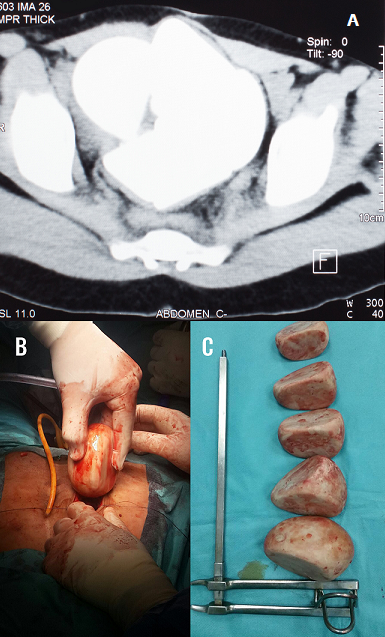

Géantes lithiases de stase sur vessie iléo-caecale

L'exstrophie vésicale est une malformation caractérisée par la déhiscence de la paroi abdominale antérieure sous ombilicale et la paroi antérieure de la vessie. Rencontrée environ dans 30000 à 40000 naissance par an, elle semble plus toucher les garçons que les filles, la dérivation externe continente semble donner de bons résultats à long terme elle n'est cependant pas dénuée de complications. Nous rapportons le cas d'une patiente âgée de 30 ans, opérée il y a 13 ans pour extrophie, ayant bénéficie d'une cystectomie avec remplacement par vessie iléo caecal, suivie pendant 5 ans puis perdue de vue. Elle se présente en mars 2017 dans un tableau de douleurs abdominales à type de pesanteur ainsi qu'une constipation évoluant dans un contexte d'apyrexie et de conservation de l'état général. L'examen retrouve une patiente en bon état général avec une cicatrice de laparotomie médiane, la valve de la poche est continente non invaginée avec des touchers pelviens sans particularités. La palpation hypogastrique retrouve une masse dure pierreuse non douloureuse. L'arbre urinaire sans préparation objective une opacité de tonalité calcique 130*110 mm ainsi qu'une disjonction symphysaire. L'échographie rénale et pelvienne objective plusieurs images hyperéchogènes avec cône d'ombre postérieur occupant tous le pelvis, deux reins de tailles normales bien différenciées sans urétèro-hydronéphrose. L'uroscanner retrouve une néo vessie siège de 5 volumineux calculs de densité calcique autour de 730 UH dont la plus volumineuses mesures 112*101mm. La fonction rénale était normale et l'examen cytobactériologique des urines a mis en évidence une infection urinaire à E COLI BLSE sensible aux carbapenèmes. Le traitement a consisté en une antibiothérapie adaptée associée à une enterocystolithotomie avec extraction laborieuse de 5 gros calculs. A l'étude spectrophotométrique les calculs sont de nature phospho-ammoniaco-magnesienne. Les suites opératoires étaient simples, l'arbre urinaire sans préparation post opératoire était stone free.